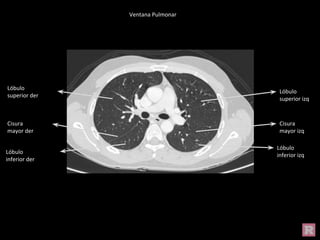

Ventana Pulmonar

Cisura

mayor der

Lóbulo

superior der

inferior der

superior izq

inferior izq

mayor izq

Cisura menor

Lóbulo medio